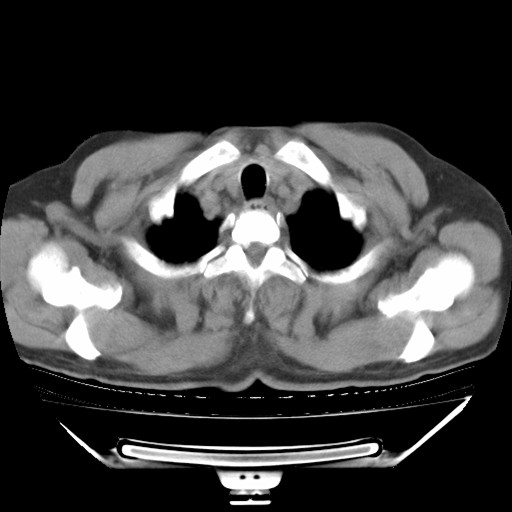

以下是引用hhcckk在2009-5-29 10:34:00的发言:[br]左下肺片絮状边缘模糊影,考虑感染,建议治疗后复查[br]